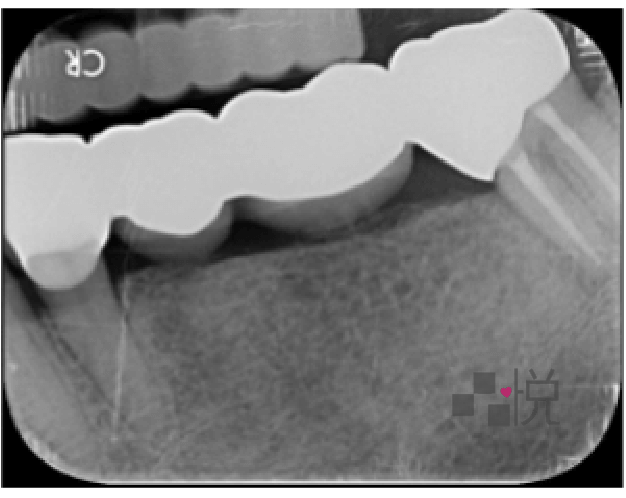

先前活動假牙戴超過二十年,早已磨損,造成咬合高度下降,臉慢慢變形,但活動假牙提供的咬力較小,當時年紀也較輕,因此沒有感到不舒服。

八年前植牙採用一樣的咬合,一開始也沒有問題,但植牙後,享用更多美食,再加上年紀增長,關節開始出現退化現象,日漸出現疼痛。

過低的咬合也讓微笑曲線不好看,臉型變得較扁,嘴角塌陷顯得嚴肅。這些都可以透過改變全口的咬合來做改善。

幸運的是王老師年輕時牙齒不好,反而一直用很高的潔牙標準要求自己,長期努力的結果,牙周狀況非常良好,只要更換部分假牙,就可以得到大幅度改善。

饒醫師先使用咬合板提高咬合高度,王老師配戴後感到關節舒適許多,甚至不敢一日不戴咬合板入睡。